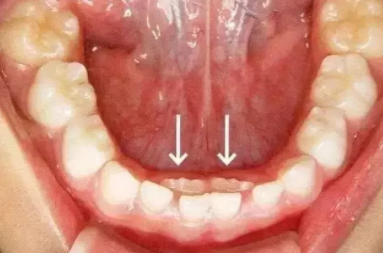

很多寶寶都會有恒牙已生乳牙未脫的情況,使得恒牙長出后出現錯位,長歪的情況,非常的影響牙齒的整體美觀,那么寶寶恒牙長出后錯位怎么辦?下面八寶網小編帶來介紹。

若在換牙年齡,家長應盡快帶孩子去看牙醫,將滯留乳牙拔出,為恒牙讓出空間;

若超過換牙年齡而乳牙未脫落,恒牙未萌出,則不要輕易拔掉;

若是恒牙先天性缺失,應盡量保持乳牙。